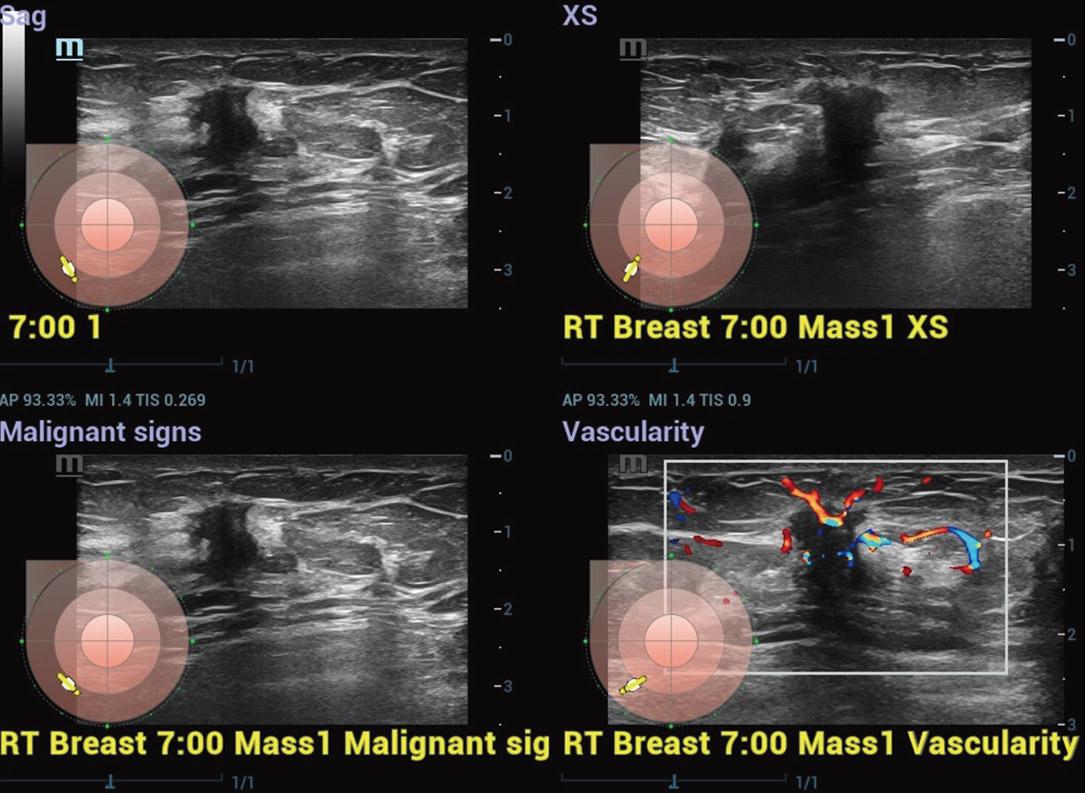

Borstkanker is wereldwijd de meest gediagnosticeerde vorm van maligniteit. Het is de meest voorkomende doodsoorzaak door kanker bij vrouwen. Vroegtijdige opsporing van borstkanker is essentieel omdat pati?nten in een vroeg stadium een betere prognose hebben. Als antwoord hierop biedt de Resona R9 Platinum Edition een oplossing voor multi-parametrische borstechografie die vroege detectie van borstkanker, nauwkeurige diagnose en behandeling van borstkanker en baanbrekend klinisch onderzoek mogelijk maakt.

M-Reference Multi-parametrische analysetools

M-Ref. C&E

M-Ref. C&E Borst kwaadaardig

M-Ref. C&E ondersteunt het weergeven van het contrast en de STE in ├®├®n vlak voor vergelijkende beoordeling van perfusie en elasticiteit.

Smart Breast kwaadaardig

Smart Breast

Smart Breast is een analyse- en rapportagetool voor borstechografie om de klinische routine van borstechografie nauwkeuriger en productiever te maken. Het systematische beheer van meerdere laesies en de beoordeling van vier vlakken garandeert meer diagnostische informatie. Ondertussen verbetert de gestroomlijnde geautomatiseerde workflow de effici?ntie bij het scannen van borsten.

Smart Thyroid

Thyroid is een analyse- en rapportagetool voor de schildklier om de klinische routine van schildklieronderzoeken nauwkeuriger en productiever te maken.

Smart Thyroid-nodule